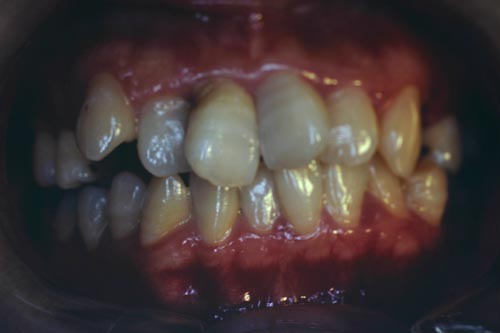

叢生の抜歯矯正の症例

Before

After

叢生ケースで4番の歯を4本抜歯し、唇側ブラケット矯正にて治療をした

年齢 30代

治療期間 2年6ヶ月

治療費用 1,000,000円

治療のリスク 特になし